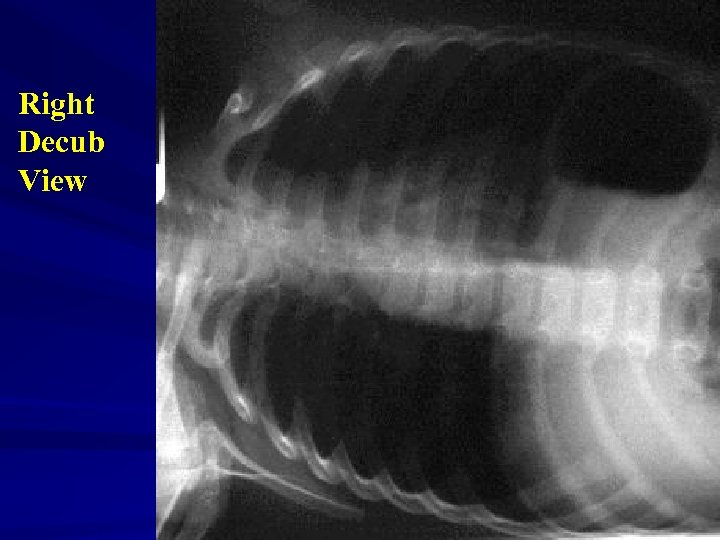

Soft Tissue Neck View

Investigations Xrays Ø Lateral neck Ø Chest – inspiratory, expiratory, decubitus views Expiratory views Overinflation (partial obstruction with inspiratory flow) Volume loss with mediastinal shift towards obstructed side (partial obstruction with expiratory flow) Atelectasis (complete obstruction)

Decubitus views Normal Smaller volumes and elevated diaphragm on side down Abnormal Hyperinflation or “normal” volumes in decub position If suspected … Need a bronchoscope to rule out or remove Foreign Body